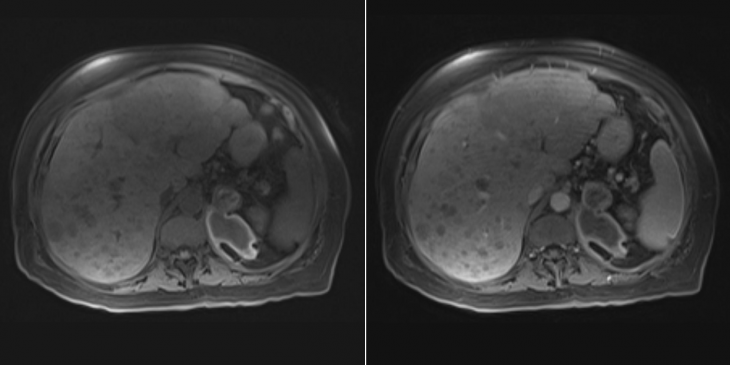

A 63-year-old man with neuroendocrine tumor (NET) metastatic to the liver undergoes magnetic resonance imaging (MRI) for evaluation of response to therapy. The patient reports an episode of left upper quadrant pain (unrelated to trauma) that occurred several weeks earlier. Noncontrast (left) and postcontrast (right) T1-weighted images with fat suppression are available for review.

What is your diagnosis?